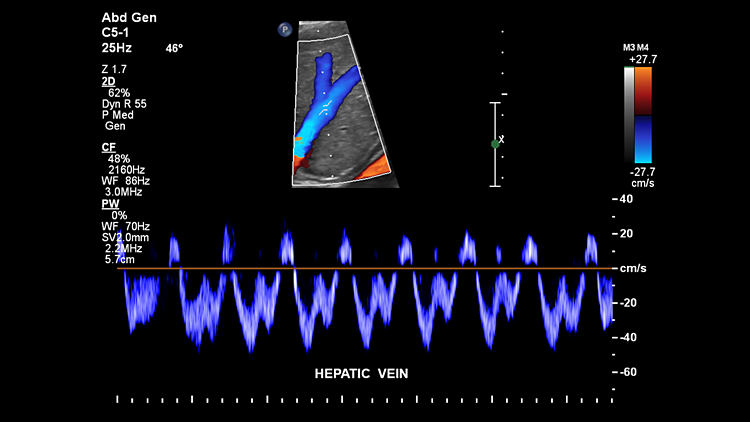

Печеночная вена, C5-1